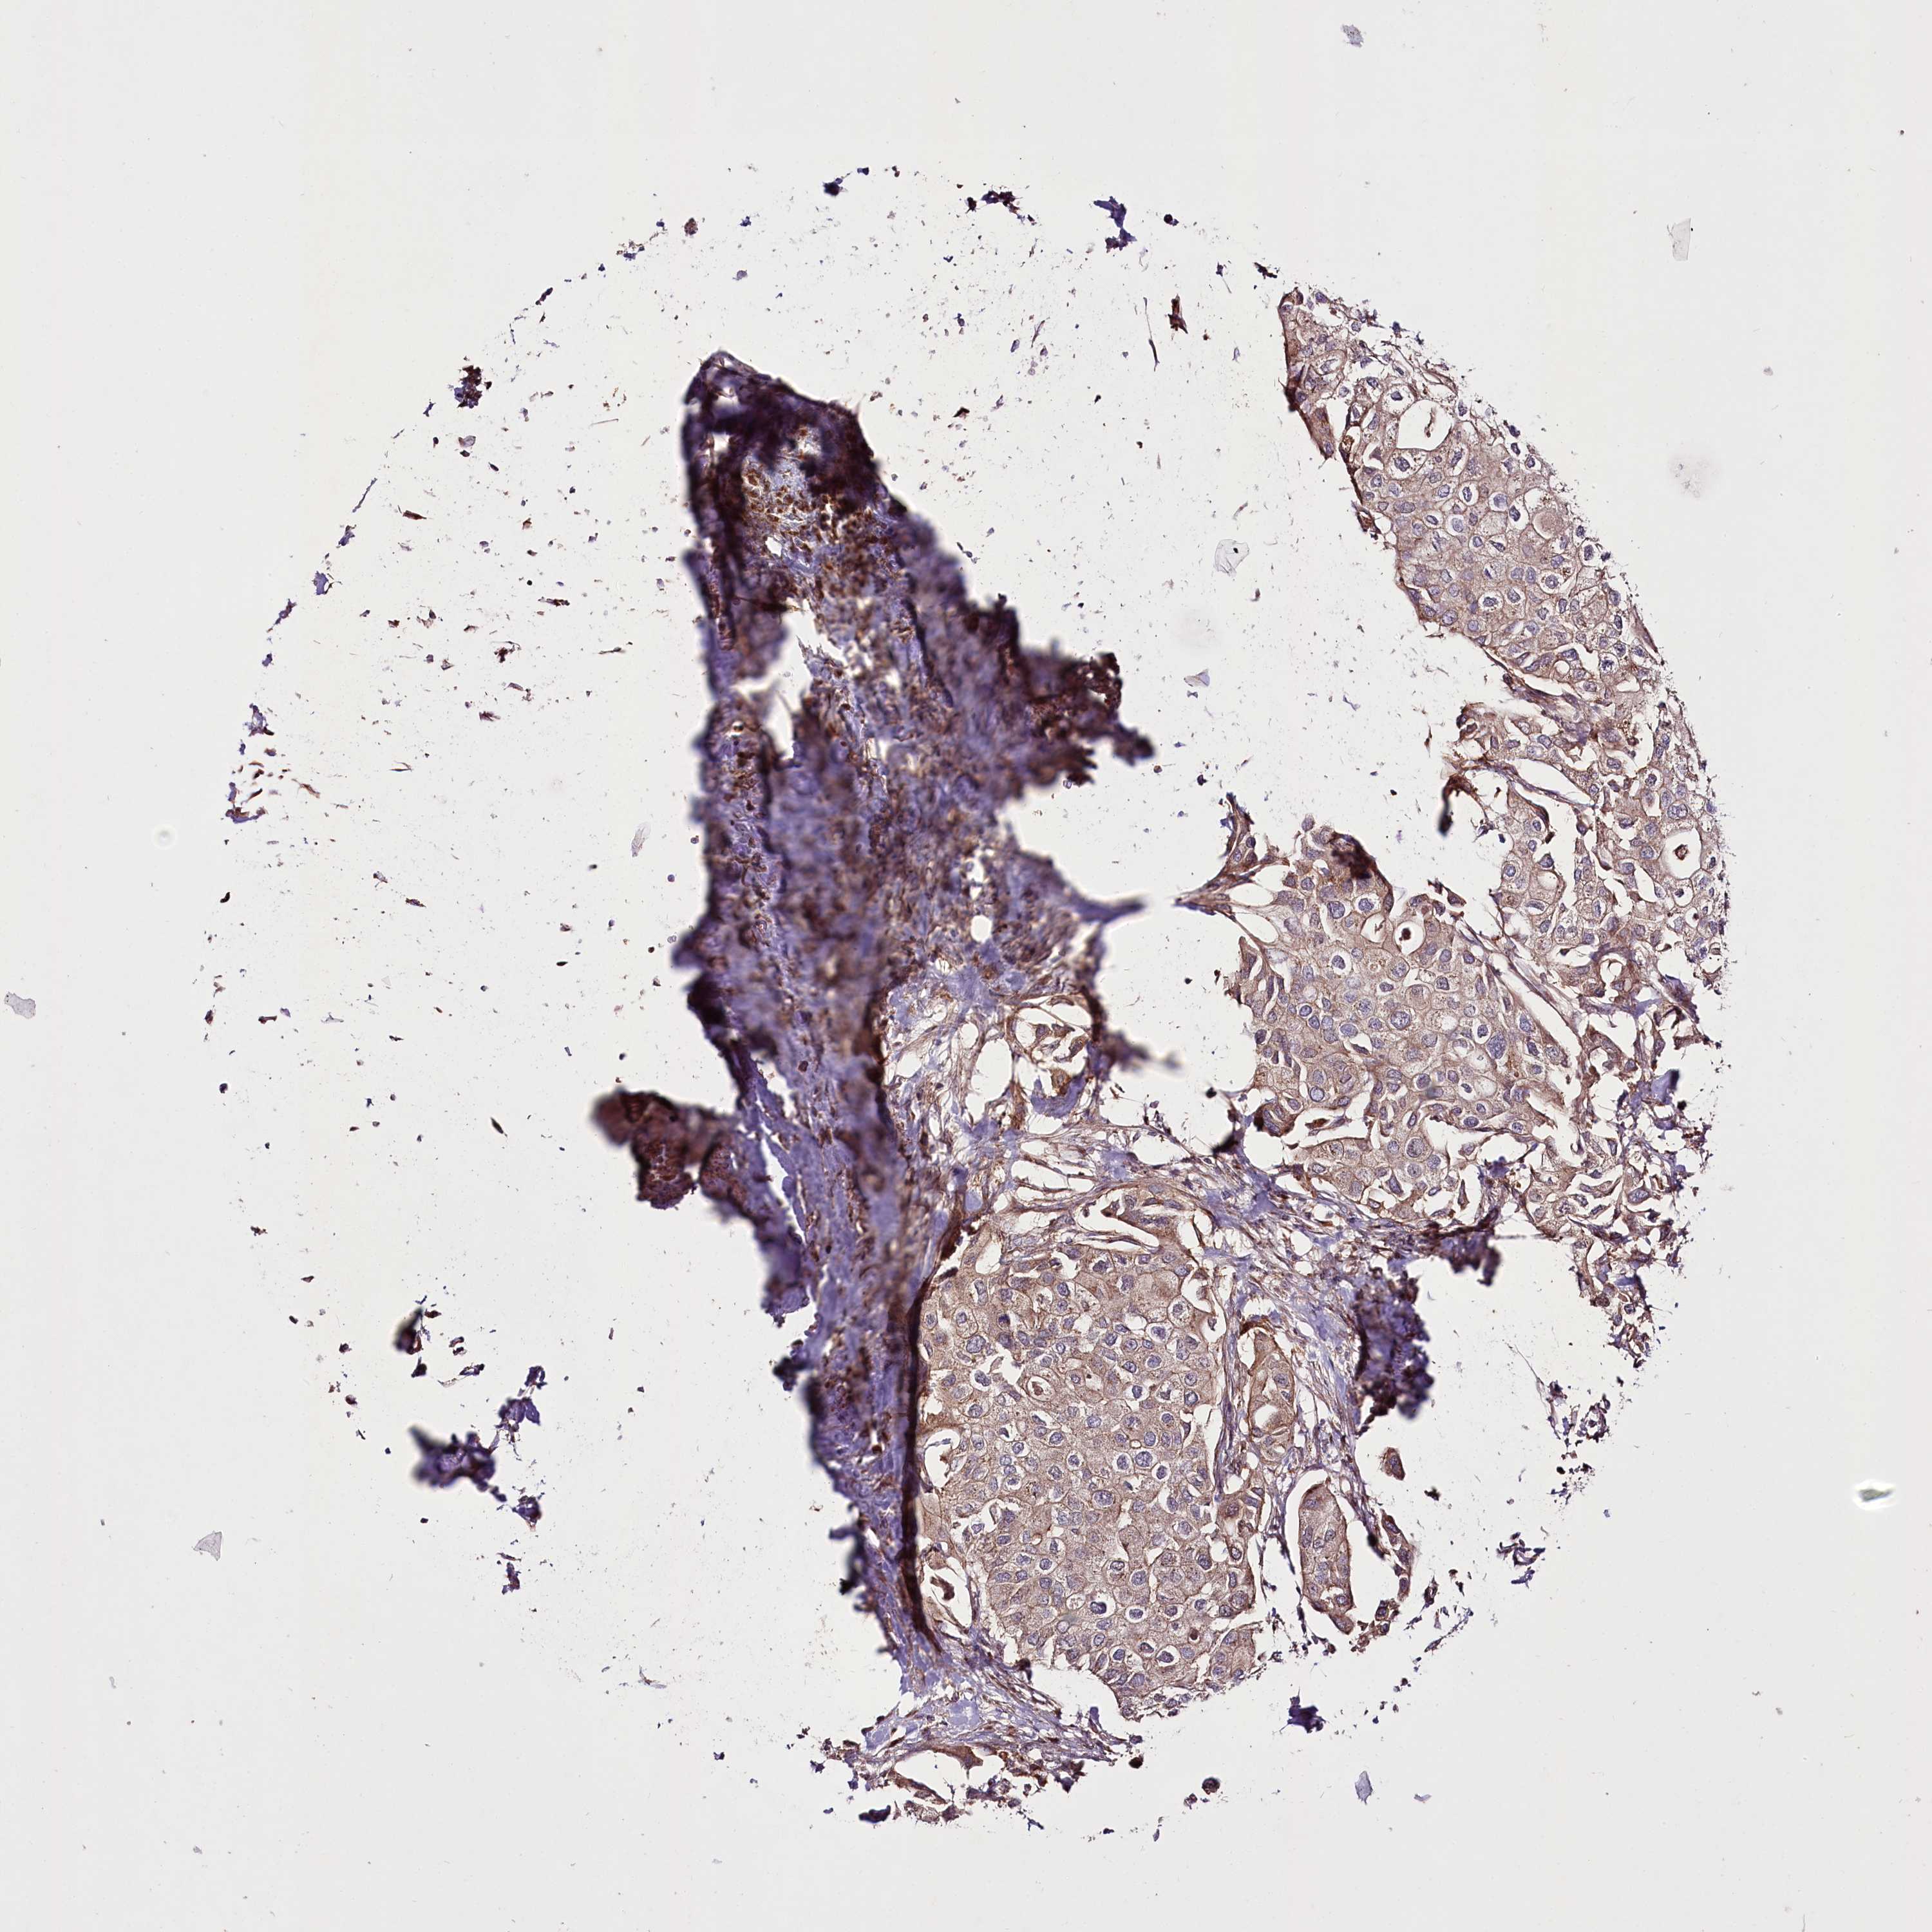

UROTHELIAL CANCER - Protein expressioni

A mouse-over function shows sample information and annotation data. Click on an image to view it in a full screen mode. Samples can be filtered based on level of antibody staining by selecting one or several of the following categories: high, medium, low and not detected. The assay and annotation is described here.

Note that samples used for immunohistochemistry by the Human Protein Atlas do not correspond to samples in the TCGA dataset.

Antibody stainingi

Antibody staining in the annotated cell types in the current human tissue is reported as not detected, low, medium, or high, based on conventional immunohistochemistry profiling in selected tissues. This score is based on the combination of the staining intensity and fraction of stained cells.

Each image is clickable and will lead to virtual microscopy that enables deeper exploration of all samples and also displays staining intensity scores, fraction scores and subcellular localization as well as patient and tissue information for each sample.

Antibody HPA038450

Antibody HPA038451

Staining

High

Medium

Low

Not detected

Intensity

Strong

Moderate

Weak

Negative

Quantity

>75%

75%-25%

<25%

None

Location

Nuclear

Cytoplasmic/membranous

Cytoplasmic/membranous,nuclear

Urothelial carcinoma, High grade

Urothelial carcinoma, Low grade

Urothelial carcinoma, NOS